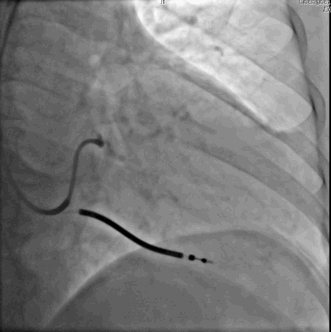

电极无法沿导丝通过!!!!

•导丝通过后扭曲血管被拉直

•但是四极电极通过仍然困难

•强行推送电极,导丝电极鞘管全部外弹

Swing技术的应用

•Swing技术:利用患者自身的心脏跳动,顶住四极导线电极,电极会逐步缓慢前行至靶静脉远端。

要点:

•避免过度用力,持续给力

•稳住导丝,透视下操作